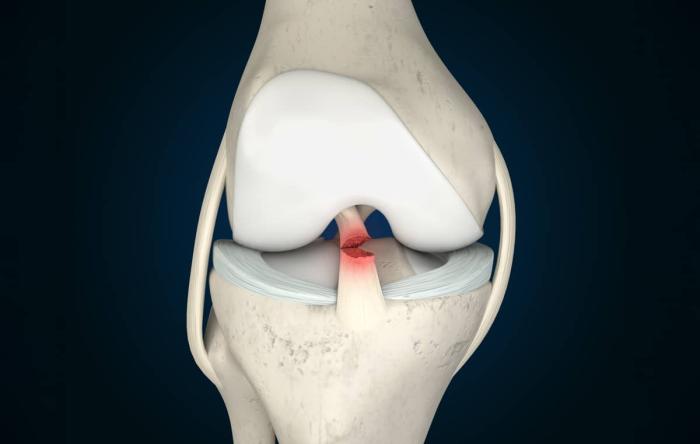

ACL surgery is performed more than 100,000 times...